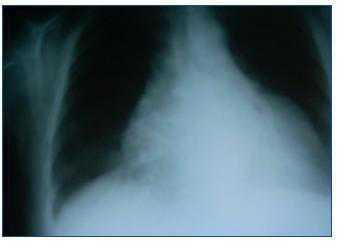

Dear Editor, Microscopic polyangiitis is a necrotising vasculitis primarily affecting the glomeruli (vasculitis limited to the kidney may be the only manifestation), and secondly, the lungs, but it is a systemic process that may affect small blood vessels in any part of the body. High blood pressure is the most common cardiovascular manifestation. We present the case of a patient with sub-acute deterioration of renal function and affected pericardium who responded well to steroid treatment. This 60-year old female patient with a history of diabetes mellitus that was diagnosed three years before, with no microangiopathy or macroangiopathy and high blood pressure during ten years which was treated with carvedilol, hydrochlorothiazide and valsartan. One year before, her creatinine level was 0.8mg/dl, GFR (MDRD) > 60 ml/min/1.73m, and systemic/urine sediment showed no abnormalities. In the six weeks prior to admission, she reported progressive weakness, followed by fever and dry cough. She did not present dyspnoea, chest pain, or diuresis alterations. The examination revealed blood pressure of 190/80mmHg, breathing well, with high jugular vein pressure, rhythmic cardiac sounds with pericardial rub, normal bilateral hemithorax ventilation and no oedema. The analysis showed haemoglobin levels of 7.7mg/dl, urea 217mg/dl, creatinine 4.5mg/dl, potassium 3.6mEq/l, 98% baseline saturation; in the urine; proteinuria of +++ and 60 red blood cells/field. The ECG was normal. The chest radiography showed severe cardiomegaly (figure 1). An emergency echocardiography showed a moderate-to-severe pericardial effusion. Ultrasound showed no kidney alterations. Treatment was started with doses of steroids at 1mg/kg/day, and the patient’s state improved considerably in a few days. With regard to the laboratory results, the direct Coombs test was negative, haptoglobin was 4g/l, LDH 370U/l, C3 and C4 within the normal range, ANA was negative, ANCA was positive, with a p-ANCA pattern. Reactivity analysed by the ELISA test corresponded to antimyeloperoxidase of 146U/ml. Proteinuria was 2g/24 hours. The percutaneous renal biopsy of a total of 17 glomerules was compatible with focal proliferative glomerulonephritis, with crescents at 50% and significant tubulointerstitial involvement. A dose of IV cyclophosphamide was recommended, and the echocardiography was repeated (a day before cyclophosphamide bolus administration) with no signs of the pericardial effusion. After a stay of 18 days, she was discharged with a creatinine value of 1.8mg/dl. In small-vessel vasculitis, it is possible to have primary or secondary cardiac involvement relating to high blood pressure, immunosuppressants, the inflammatory state and the kidney disease that can contribute to developing cardiac hypertrophy, bacterial endocarditis and coronary disease.1,2 As a primary manifestation of the disease, cardiac involvement is more frequent in Churg-Strauss disease, where 13-47%1,3 of all patients have a myocardial, endocardial or pericardial lesion. With regard to the incidence rate for pericardial involvement, whether in the form of acute pericarditis and pericardial effusion or as chronic constrictive pericarditis, its range is estimated between 8 and 32% in Churg-Strauss syndrome and 19% in Wegener’s granulomatosis.5 With regard to microscopic polyangiitis, its unusual presentation as a pericardial effusion caught our attention, and in fact, the literature we consulted contained no references to such an event. Finding it in inflammatory state and the kidney disease that can contribute to developing cardiac hypertrophy, bacterial endocarditis and coronary disease.1,2 As a primary manifestation of the disease, cardiac involvement is more frequent in Churg-Strauss disease, where 13-47%1,3 of all patients have a myocardial, endocardial or pericardial lesion. With regard to the incidence rate for pericardial involvement, whether in the form of acute pericarditis and pericardial effusion or as chronic constrictive pericarditis, its range is estimated between 8 and 32% in Churg-Strauss syndrome and 19% in Wegener’s granulomatosis.5 With regard to microscopic polyangiitis, its unusual presentation as a pericardial effusion caught our attention, and in fact, the literature we consulted contained no references to such an event. Finding it in this case was achieved by hearing the pericardial rub; together with a compatible radiography, this led us to order the echocardiography that confirmed our diagnosis. She began steroid treatment early, with an excellent response. As a result of this experience, we must consider the possibility of pericardial involvement in this type of vasculitis. Proper examination and evaluation of simple complementary tests that are available in every hospital continues to be the fundamental pillar of a correct diagnostic and therapeutic approach.

Figure 1. Cardiomegaly without other signs suggesting heart failure.